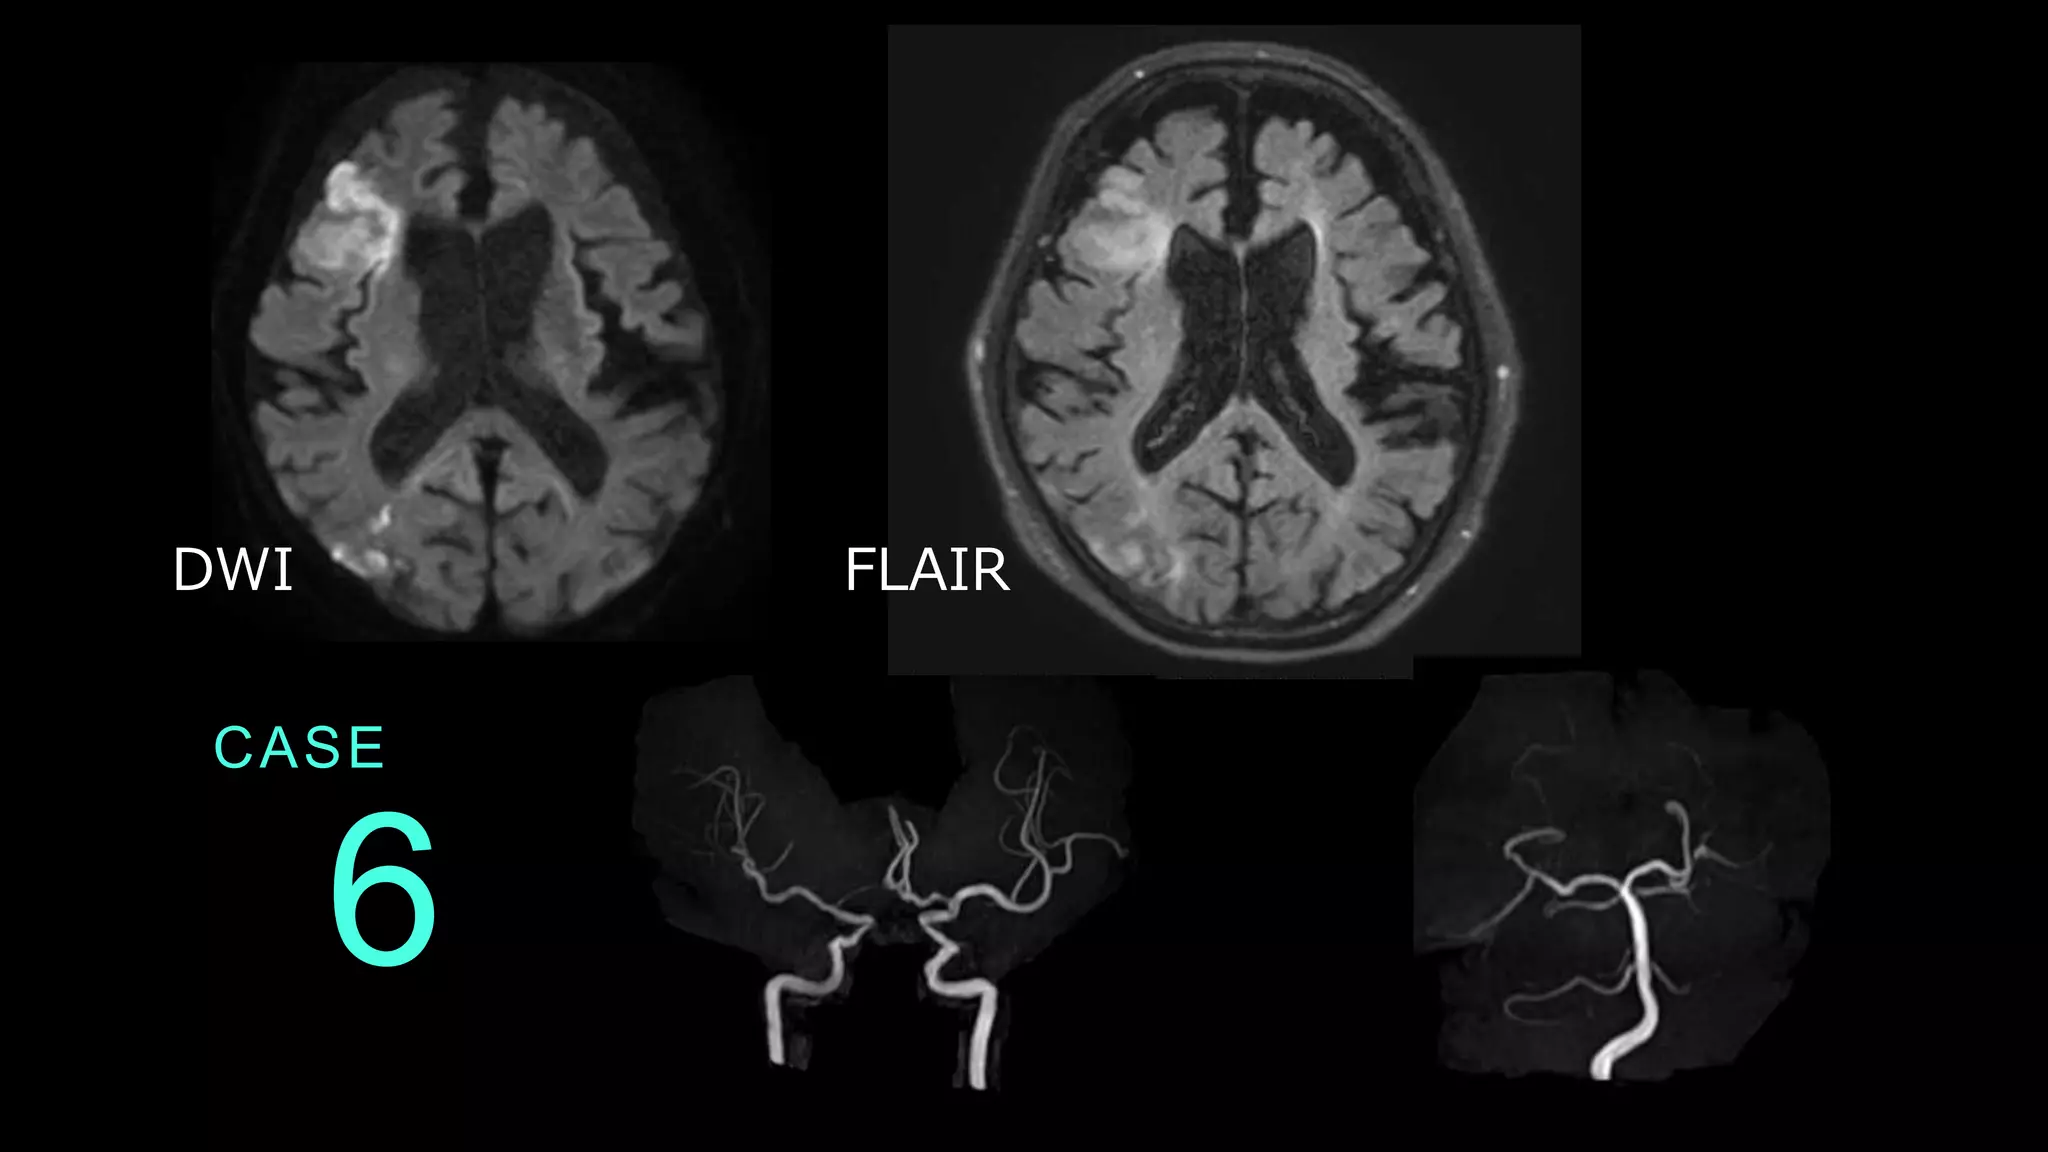

CASE 6 DWI FLAIR

CASE 6 DWIでは右前頭葉の皮質と白質に高信号病変を認める 。また、側頭葉の皮質・白質にも高信号病変がある。 これら病変は、FLAIRでも淡い高信号変化を認める。

CASE 6 ACAは両側左のICAからの血流が主である。 左のVAは描出なく、先天性低形成が疑われる。 これらはnormal variantsと推測される。

CASE 6 コメント:アテローム血栓性脳梗塞症例。皮質と白質 を含む病変であること、前頭葉と側頭葉にあること、 DWIとFLAIRでHIGHであることを述べる。